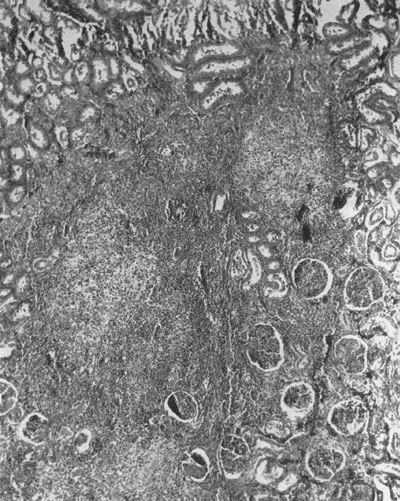

Las lesiones renales permanentes que se observan en niños después de padecer una o varias infecciones urinarias (IU) febriles, han recibido varias denominaciones en los últimos decenios. El primer nombre empleado fue el de “pielonefritis crónica”3,4. Se trata de un término difícil de comprender en la actualidad. En necropsias de pacientes, sobre todo niños, fallecidos después de padecer una pielonefritis aguda5,6 y en animales de experimentación con IU inducidas7, se observaba la persistencia de bacterias en el parénquima renal junto a zonas de fibrosis y de desaparición de glomérulos (figuras 1 y 2). Este hecho puede atribuirse a la ausencia de antibióticos eficaces en su momento hace decenios y a la difícil llegada de esos fármacos a las zonas cicatrizales correspondientes a las zonas de parénquima renal destruido7 y quería indicar que podría permanecer una población bacteriana en la pelvis y parénquima renal después de una IH febril. Este hecho insólito y no mencionado en la actualidad, podría explicar la recurrencia de algunos de casos de IU. En los años 60 del pasado siglo se enfatizó la relación entre pielonefritis crónica y RVU2,8.

Los artículos de Shapiro et al. publicados a finales de la década de los años 50 del pasado siglo demostraron de forma clara que la pielonefritis experimental inducida en ratas causaba una inflamación que devenía en fibrosis y perdida de zonas de parénquima renal (figuras 1 y 2)7,16. Esos autores inocularon por vía intracardiaca cepas de escherichia coli, proteus morganii y streptococcus zymogenes, es decir, en ausencia de RVU. Sorprendentemente, observaron que las lesiones residuales renales eran diferentes según el tipo de bacteria inoculada. Así, observaron que la infección causada por escherichia coli era autolimitada pero con lesiones residuales crónicas. Por otra parte, proteus morganii producía una marcada destrucción renal, formación de cálculos e hidronefrosis. El comportamiento virulento distinto de los tres tipos bacterianos puede explicarse por poseer propiedades antigénicas distintas, es decir, con una capacidad diferente para adherirse a los receptores de las fimbrias existentes en el urotelio y el tejido renal.

Figura 1. Riñón pielonefrítico seis semanas después de una infección producida por Proteus. Se observa fibrosis y amontonamiento de glomérulos

(X70)7

Figura 2. Riñon pielonefrítico seis semanas después de una infección producida por Proteus. Se observa fibrosis (X16) en un tono pálido en las áreas lesionales (light blue in Mallory Stain)7